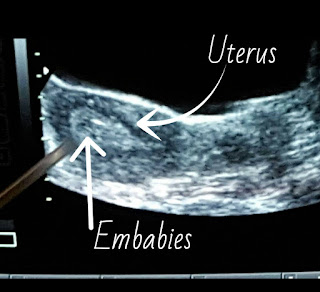

The embryos are wheeled in an incubator where we were able to see them up on a screen.  The embryologists then sucked the little embabies into a tiny little catheter and then were given to the doctor to place inside my uterus.  The procedure was completely pain free, minus some discomfort from having a completely full bladder.  I was laid flat and had another acupuncture session and was able to get up an hour later.

We transferred two beautiful little babies.

The embryo on the right is fully hatched while the embryo on the left was in the process of hatching. The really neat part is in about four hours the hatching embryo should be fully hatched and would look like its sibling on the right.